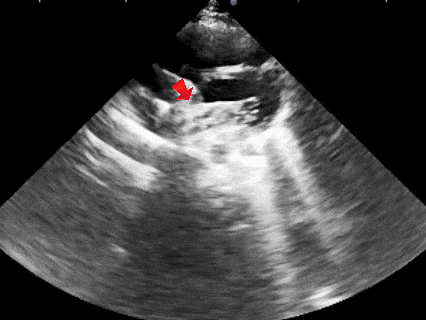

成型

牵拉成型线使得封堵器双盘扣合住间隔,封堵器骑跨于缺损左右两侧

锁定

锁定后,超声下观察封堵器盘面平整贴壁,成型良好

锁定后牵拉

牵拉试验时,超声下观察封堵器,封堵器结构稳定无散开,锁定成功